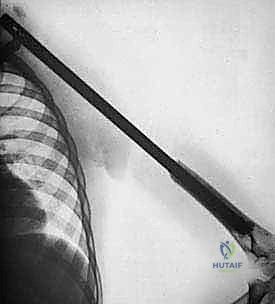

1. التصوير الشعاعي (X-Rays)

الخطوة الأولى والأساسية. تظهر الأشعة السينية تدمير العظم، رد فعل السمحاق (Periosteal reaction)، وتساعد في تحديد طبيعة الورم (هل يبدو حميداً أم خبيثاً؟).

3. التصوير المقطعي المحوسب (CT Scan)

يُستخدم لتقييم التدمير القشري للعظم بشكل أدق. الأهم من ذلك، يتم إجراء تصوير مقطعي للصدر (CT Chest) للبحث عن أي نقائل سرطانية في الرئتين، حيث أن الرئة هي المكان الأول لانتشار ساركوما العظام.

- القياسات الدقيقة (Templating): باستخدام برامج الكمبيوتر المتقدمة وصور الأشعة المقطعية والرنين، يقوم الدكتور هطيف بحساب الطول الدقيق للعظم الذي يجب استئصاله (لضمان حواف آمنة خالية من السرطان)، ويقيس قطر القناة النخاعية لاختيار حجم الطرف الصناعي المناسب.